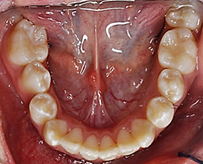

Al analizar las fotografías intraorales revelaron lo siguiente (Figura 2): Fotografía frontal: líneas medias dentales no coincidentes la inferior se encuentra con una desviación de 2 mm hacia la derecha, mordida abierta y caninos superiores ectópicos. (A). Fotografía lateral derecha (B) e izquierda (C): Clase II molar, clase canina no aplica debido a que los caninos no se encuentran en el arco.

Fotografía oclusal superior: Forma de arcada ovoide, apiñamiento en el sector anterior, palatinización de las piezas 1.2 y 2.2, piezas 1.3 y 2.3 ectópicas, paladar profundo (D). Fotografía oclusal inferior: Forma de arcada oval, lingualización de las piezas 4.5 y 4.6, ausencia de la pieza 3.7 (E). Fotografía de resalte: La sobremordida horizontal y vertical de -2 mm (F).